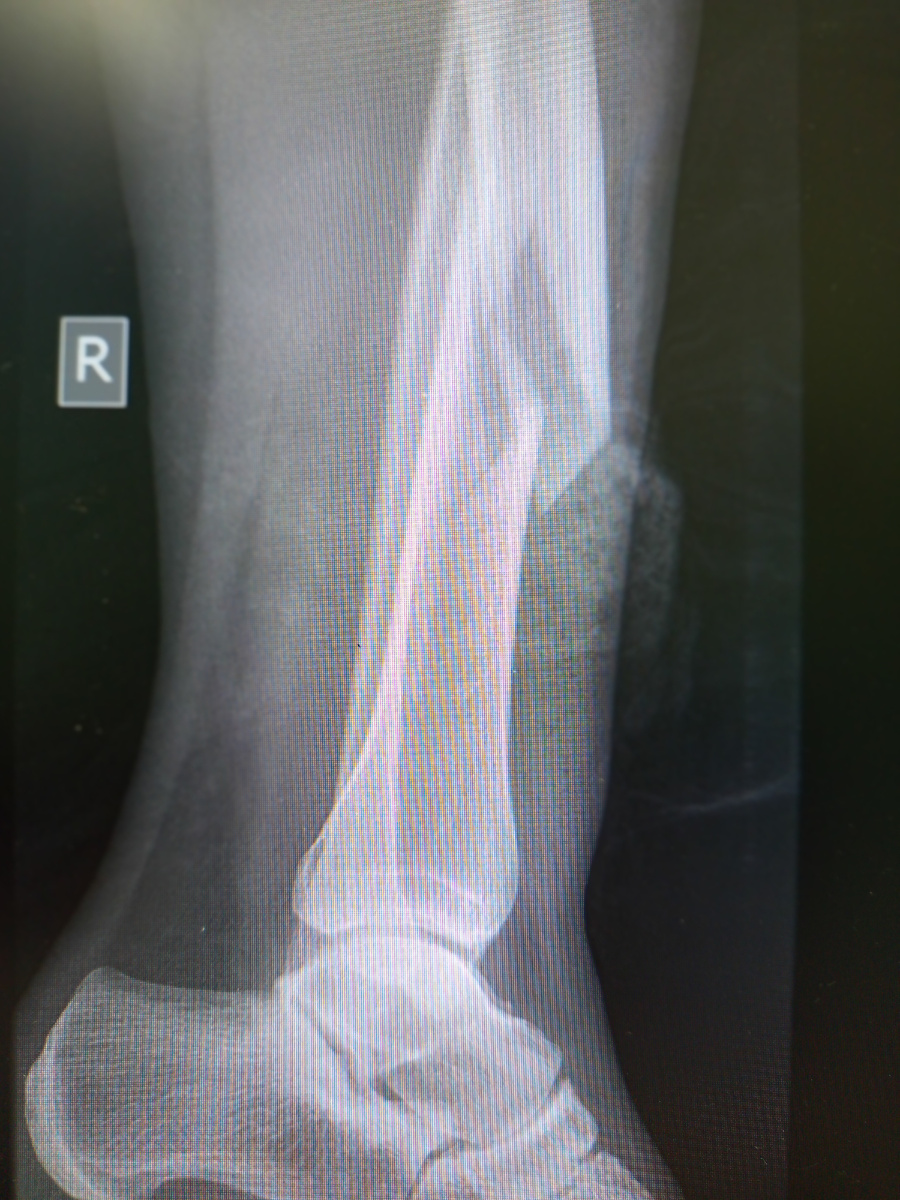

Завозят каталку , женщину сопровождают родственники.

Открытый перелом. Да , елки палки, когда все это прекратится? Когда пациент выдаст "шок" прям в кабинете?

Женщина поскользнулась дома , на разлитой воде.

Сняли только так , просто побоялись поворачивать ногу, пациентка ее чувствует и плачет от боли.

Минут через пятнадцать после осмотра травматолога завозят опять, назначили колено , на той же конечности.

И вправду, там еще подломила.

Представляете , если мы ротировали ногу? Жесткий перелом, обычное недоразумение , несчастный случай.

Пациентку сразу же подняли в оперу, на временную внешнюю фиксацию костей. В понедельник поставят в план.